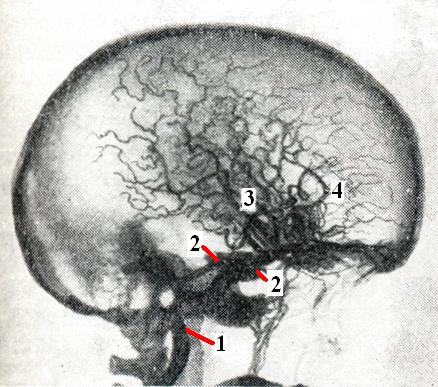

Артерио-синусные соустьяАртерио-синусные соустья (греческое arteria + латинское sinus пазуха, углубление) — патологические соустья между артериями мозга и венозными синусами твердой мозговой оболочки. Возникают в результате повреждения сосудов и отводят артериальный кровоток в венозную систему, минуя обычное кровеносное русло, действуют как шунтирующая система. К артерио-синусным соустьям относятся, в частности, сонно-пещеристые (каротидно-кавернозные) соустья. К этому же виду сосудистой патологии относят и сонно-яремные (каротидно-кавернозные) соустья, которые близки к ней по этиологии и клиническим проявлениям. Все эти соустья в патофизиологическом отношении не отличаются от артерио-венозных аневризм, однако морфологически они не являются истинными артерио-венозными аневризмами. Каротидно-кавернозные соустья.Образуются при прорыве внутренней сонной артерии в полость кавернозного синуса (рис. 1). Разрыв может быть связан с травмой или наступает спонтанно при атеросклерозе и артериальной гипертензии. Травматические разрывы обусловлены преимущественно гидравлическим ударом крови по стенке артерии в момент повреждения головы, реже — прямым механическим воздействием извне (например, при переломе основания черепа или при проникающем в полость черепа ранении).

Артериальная кровь, поступая под большим давлением в кавернозный синус, устремляется затем по его дренажной системе и может оттекать по следующим путям: 1) передний путь — по глазничным венам в вены лица; 2) контрлатеральный путь — по хорошо развитым межкавернозным анастомозам в противоположный кавернозный синус; 3) базальный путь — по базальной вене в большую вену мозга (Галена); 4) нисходящий путь — по базальному сплетению в переднее венозное сплетение позвоночника; 5) заднелатеральный путь — по каменистым синусам в поперечный и сигмовидный синус; 6) конвекситальный путь — по верхней анастомотической вене (Тролара) и венам, расположенным в области латеральной борозды, в верхний сагиттальный синус и по нижней анастомотической вене (Лаббе) — в поперечный синус; 7) твердооболочечный путь оттока по венам твердой мозговой оболочки в верхний сагиттальный и поперечный синусы. Имеются и другие, менее важные, пути дренажа. |